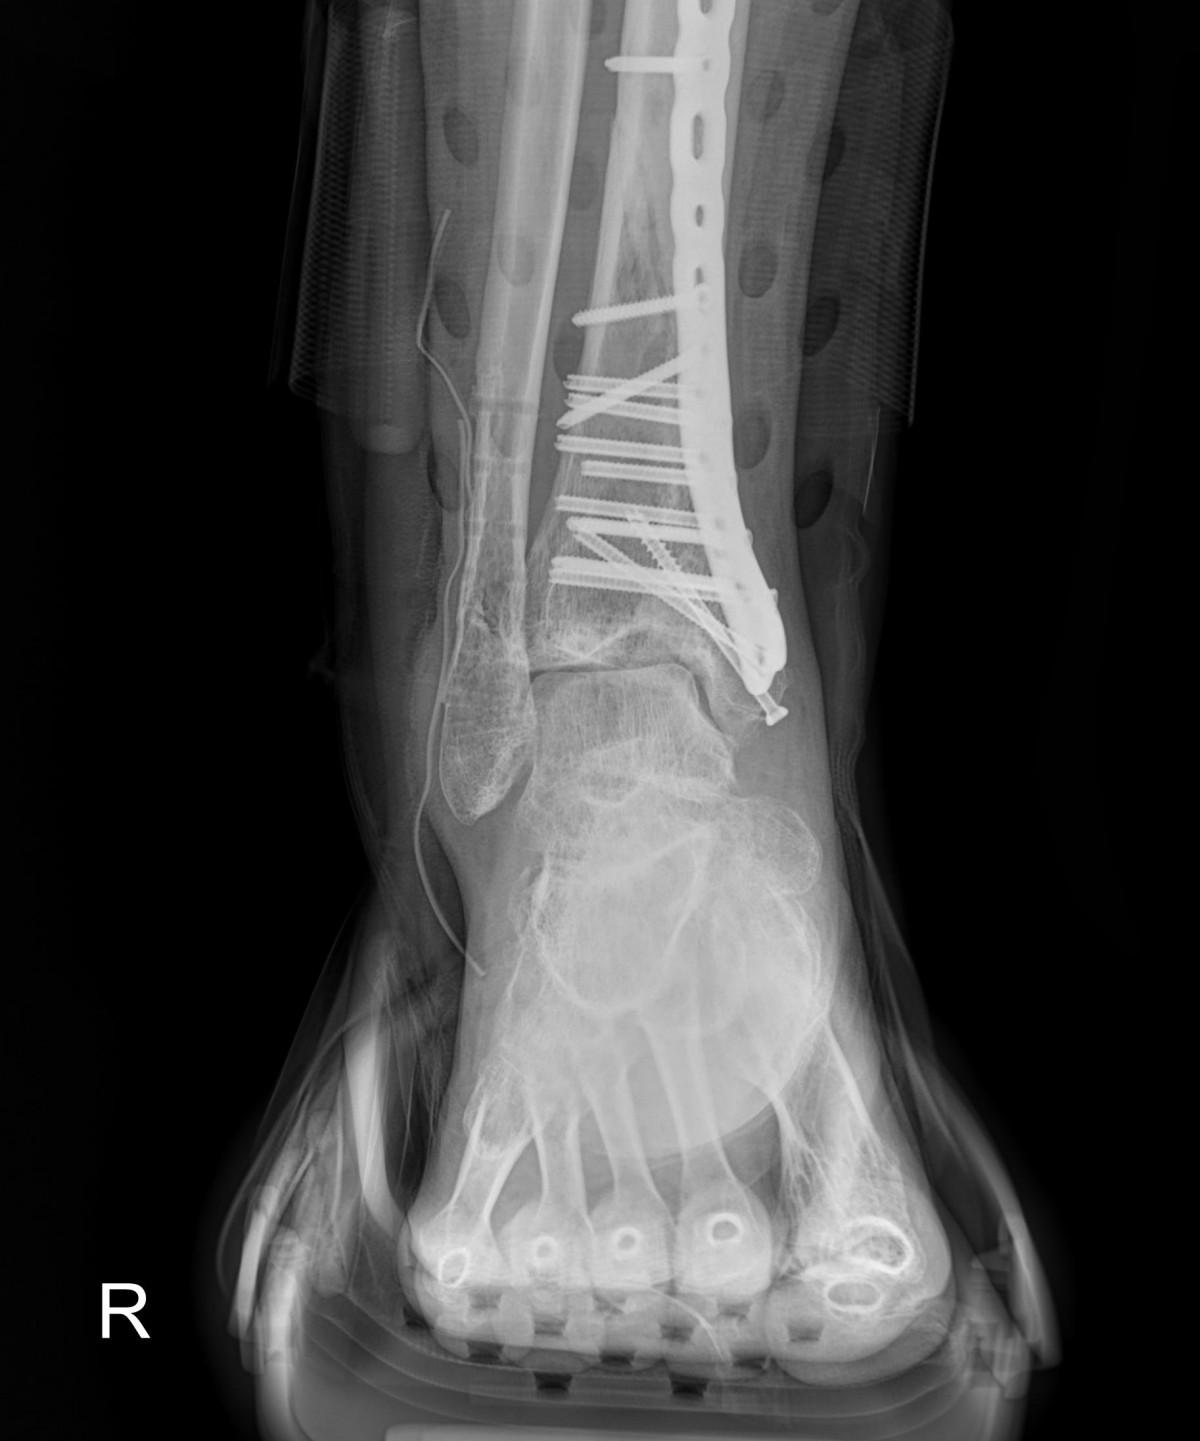

배우한원장님 발목 골절 수술 후 부분 금속물 제거술 정원O 환자

작성자 최고관리자 댓글 0건 조회 1,287회 작성일 22-11-01 15:16

dad3db92c7038bca28d5e9bbf35287bf_1667283366_1483.jpg

dad3db92c7038bca28d5e9bbf35287bf_1667283380_1308.jpg